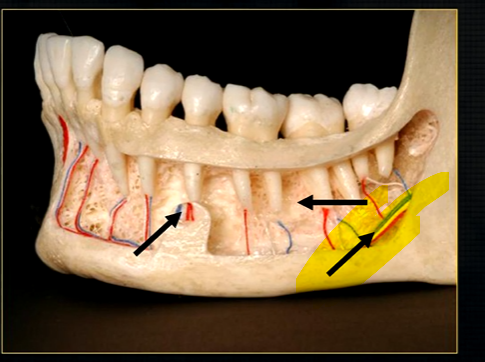

left hand side of the mandible buccal surface has been removed

roots of the teeth protrude in the underlying trabecular bone

inferior dental nerve

mental nerve - coming out of the mental foramen

reveals honeycombed pattern of trabecular bone

dense outline of the individual sockets of the teeth

cortical bone which forms the lower border

periapical region

can see honeycombed pattern

mental foramen - black radiolucency - near 1st and 2nd premolars

sockets of the teeth are represented by thin, white, opaque lines → ‘ lamina dura’

dense, white, radiopaque line → dense bone of mylohyoid ridge

underneath mylohyoid ridge - looks more radiolucent → this is due to the lingual indentation of submandibular fossa

dense cortical bone of the lower border